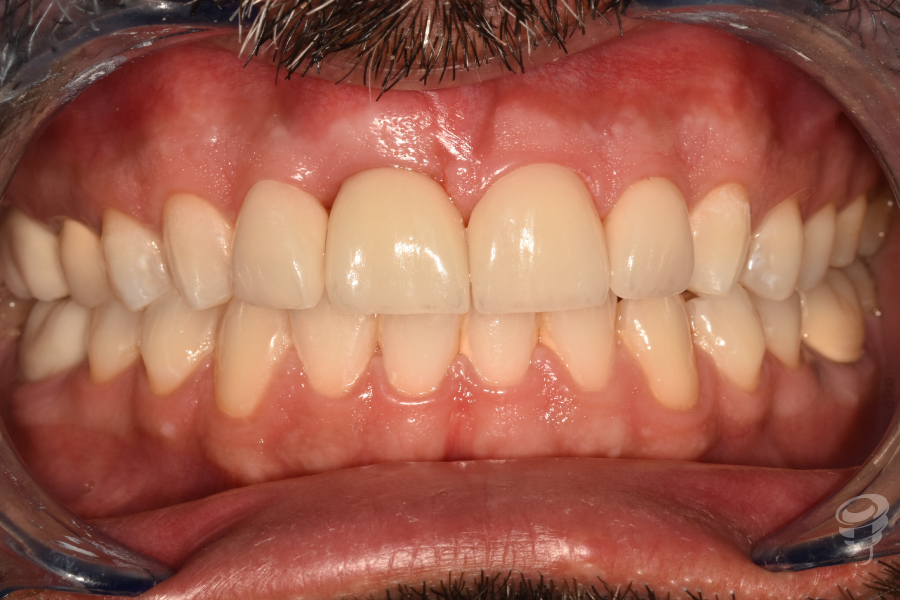

Caso Clínico | Rehabilitación Estética Integral con implante inmediato, injerto óseo y de tejido conectivo y carillas de cerámica en incisivo central superior fracturado

- Caso clínico: Paciente masculino de 45 años con fractura irreparable del incisivo central superior derecho (11) previamente tratado con una endodoncia y unión colado, fracturado por trauma oclusal. Se realizó extracción atraumática, colocación de implante inmediato, injerto óseo xenogénico mezclado con hueso antólogo del fresado, e injerto de tejido conectivo subepitelial para optimizar el perfil de emergencia. A los 4 meses se colocó corona implanto-soportada de zirconio y carillas de disilicato de litio en dientes 12 y 21.

- Resultados: A los 24 meses, se observó osteointegración completa, contorno gingival estable, armonia estética y alta satisfacción del paciente.

Resultado

Revisión a los 24 meses